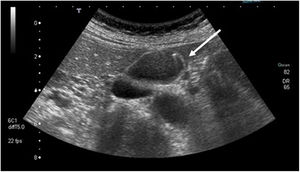

| Adenoma | Risk of malignant degeneration; may be sessile or pedunculated.Most frequent histologies: tubular, papillary or tubulopapillary | Homogenous on ultrasound, with echogenicity similar to the liver (Fig. 3). |